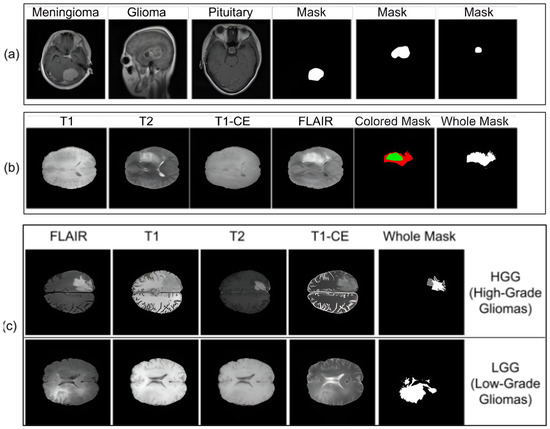

Multi-Scale Atrous Feature Fusion Based on a VGG19-UNet Encoder for Brain Tumor Segmentation

by Shoffan Saifullah and Rafał Dreżewski

Appl. Sci. 2026, 16(8), 3971; https://doi.org/10.3390/app16083971 - 19 Apr 2026

Accurate brain tumor segmentation from magnetic resonance imaging (MRI) remains challenging due to heterogeneous tumor morphology, intensity variability, and multi-scale structural complexity. This study proposes a DeepLabV3+-based segmentation framework integrating a VGG19-UNet encoder, Atrous Spatial Pyramid Pooling (ASPP), and low-level feature refinement to [...] Read more.

Accurate brain tumor segmentation from magnetic resonance imaging (MRI) remains challenging due to heterogeneous tumor morphology, intensity variability, and multi-scale structural complexity. This study proposes a DeepLabV3+-based segmentation framework integrating a VGG19-UNet encoder, Atrous Spatial Pyramid Pooling (ASPP), and low-level feature refinement to simultaneously capture hierarchical semantics and boundary-sensitive spatial details. The architecture enhances receptive field coverage without additional downsampling while preserving fine-grained contour information during reconstruction. Extensive evaluation was conducted on the Figshare Brain Tumor Segmentation (FBTS) dataset and the BraTS 2021 and BraTS 2018 benchmarks, focusing on Whole Tumor segmentation across multiple MRI modalities and tumor grades. Under five-fold cross-validation, the proposed model achieved a mean Dice Similarity Coefficient of 0.9717 and Jaccard Index of 0.9456 on FBTS, with stable and competitive performance across FLAIR, T1, T2, and T1CE modalities in both HGG and LGG cases. Boundary-level analysis further confirmed controlled Hausdorff Distance and low Average Symmetric Surface Distance. Statistical validation and ablation analysis demonstrate consistent improvements over baseline U-Net configurations. The proposed framework provides a robust and computationally efficient solution for automated brain tumor segmentation across heterogeneous datasets. Full article